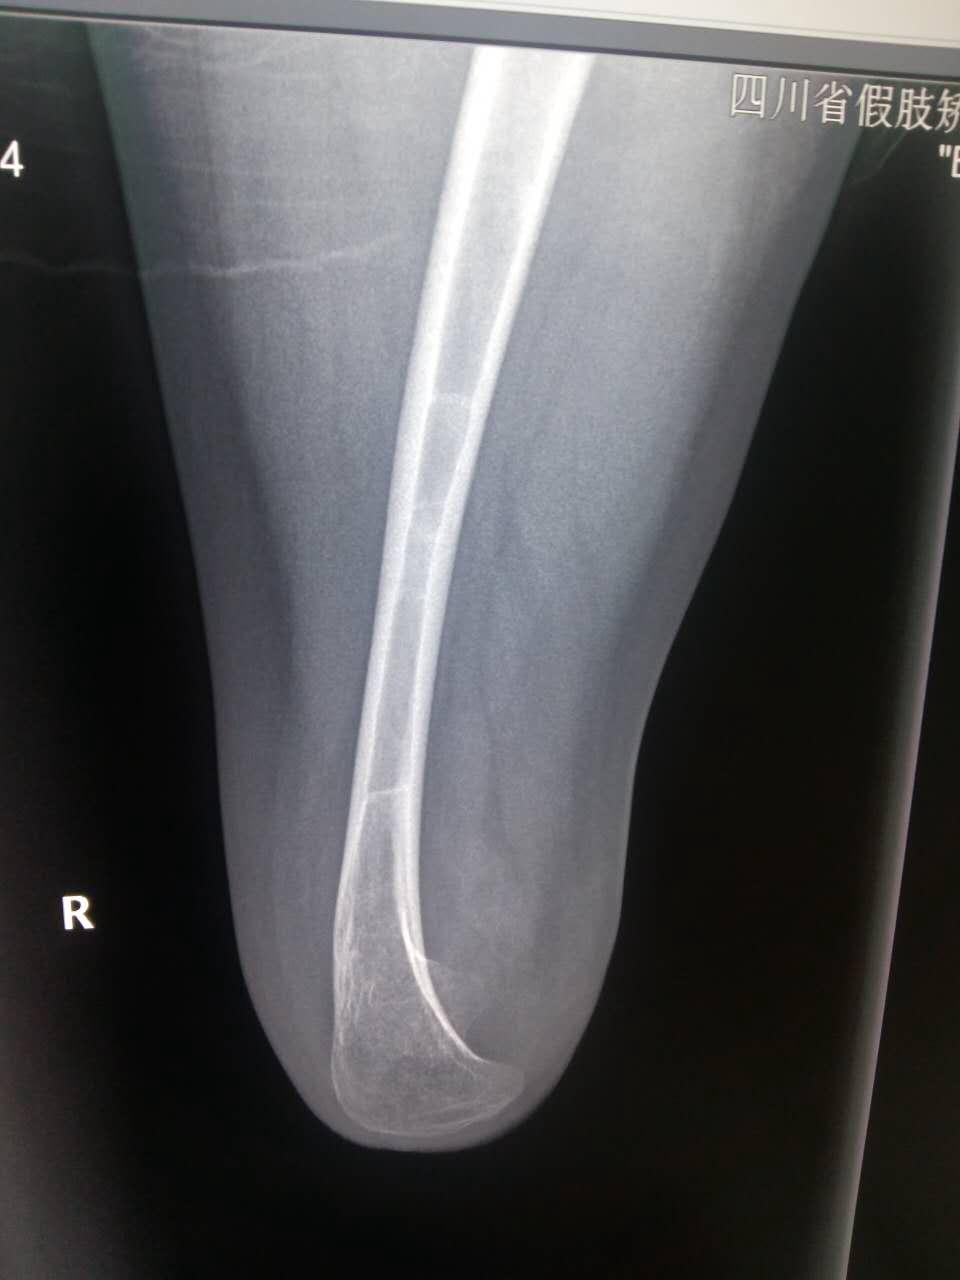

截肢二十多年,请各位老师指点一下这张x光片

右下肢股骨以下部位缺如。股骨未见明显异常。